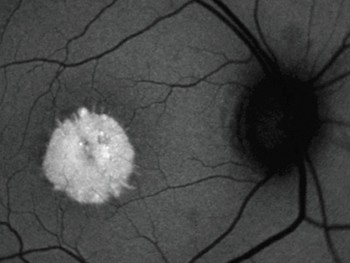

A Angiografia Fluoresceínica (AF), ou Angiofluoresceinografia, é um exame de grande importância no estudo das doenças que atingem a retina, coróide e nervo óptico. Doenças como Retinopatia Diabética, Degeneração Macular Relacionada à Idade (DMRI), Degenerações retininas hereditárias, Doenças oclusivas vasculares, entre outras, têm indicação para realizar esse exame, que apesar do nome complicado, é relativamente simples em sua realização, porém necessita grande experiência na área de retina e vítreo para a sua interpretação.

Nesta nova tecnologia pode se realizar auto-fluorescência que é uma frequencia que capta os brilhos prórprios dos tecidos. Pode ser útil em avaliar drusas e auxiliar no diagnóstico diferencial de lesões pigmentadas como nevus.